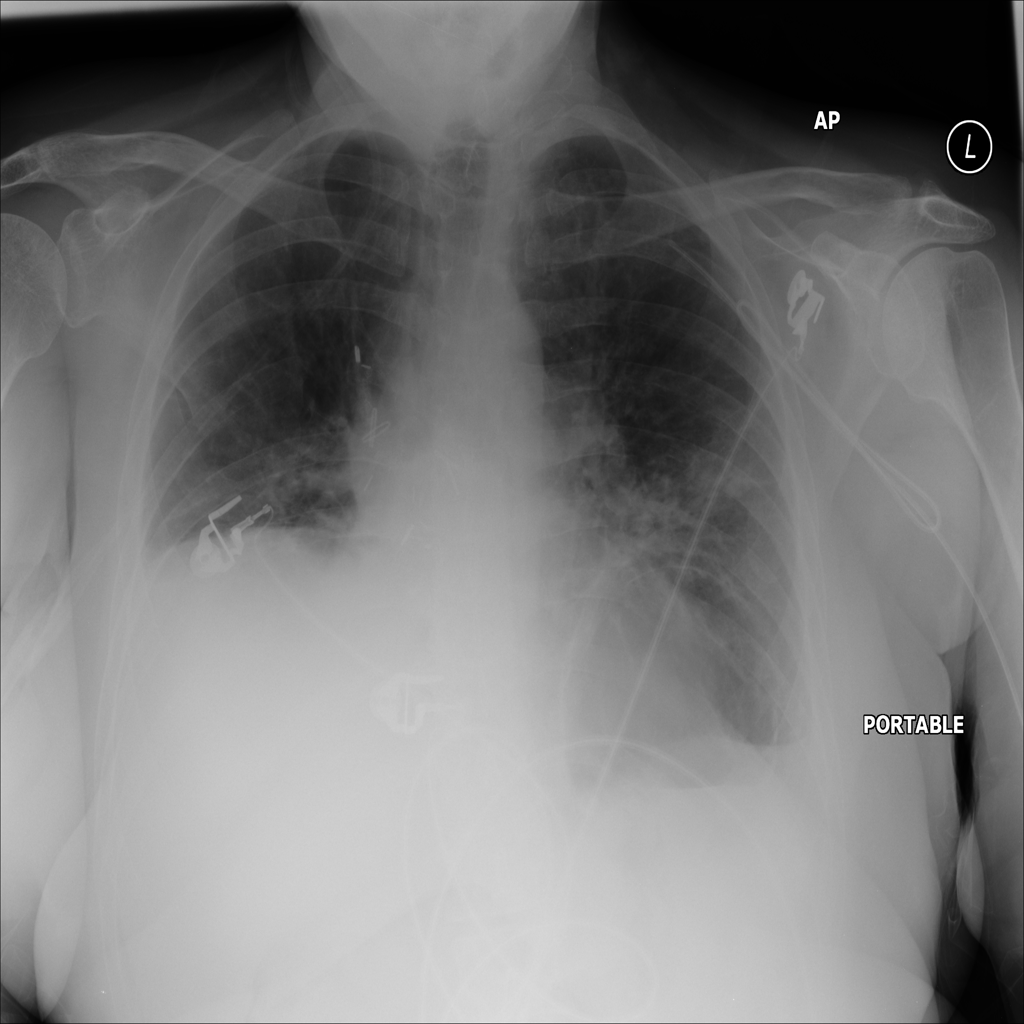

PAT-E81B · IMG-000Effusion

PAT-E81B · IMG-000

PA